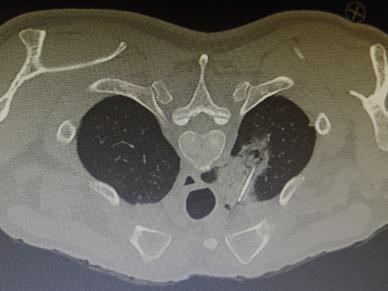

1.精准定位:医生通过CT影像锁定肿瘤位置,像导航一样精准规划“进攻路线”。

2.细针穿刺:用一根比笔芯还细的针,避开重要血管和器官,直达肿瘤“老巢”。